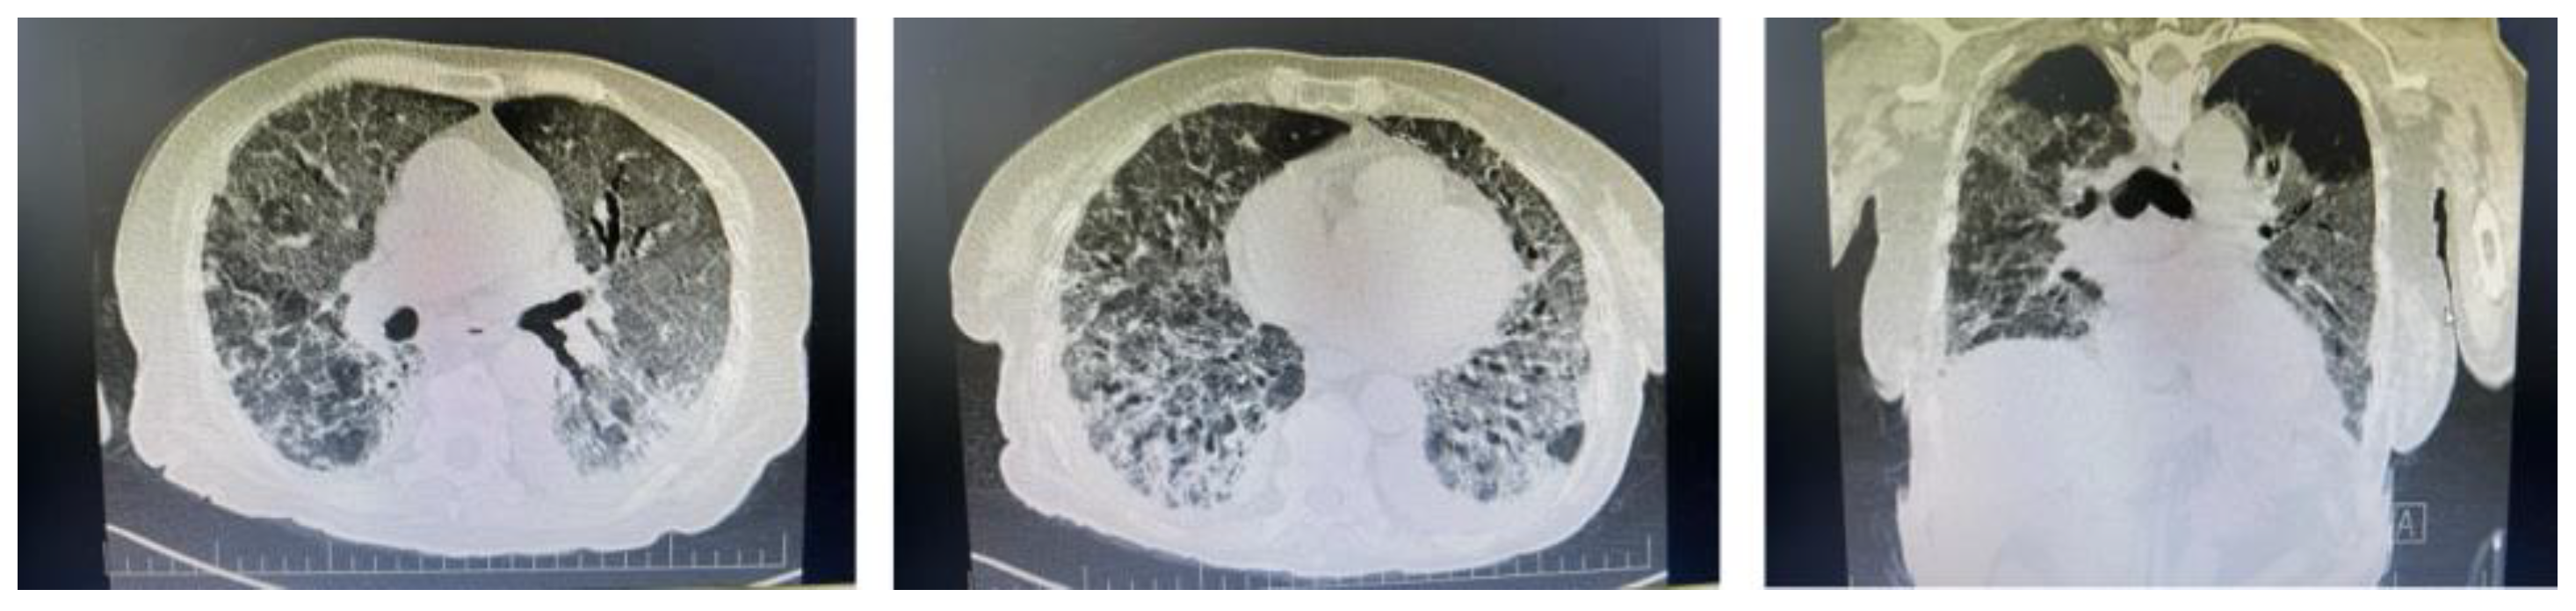

- Egashira, R. High-Resolution CT Findings of Myositis-Related Interstitial Lung Disease. Medicina 2021, 57, 692. [Google Scholar] [CrossRef]

- Tanizawa, K.; Handa, T.; Nakashima, R.; Kubo, T.; Hosono, Y.; Aihara, K.; Ikezoe, K.; Watanabe, K.; Taguchi, Y.; Hatta, K.; et al. The prognostic value of HRCT in myositis-associated interstitial lung disease. Respir. Med. 2013, 107, 745–752. [Google Scholar] [CrossRef] [PubMed]